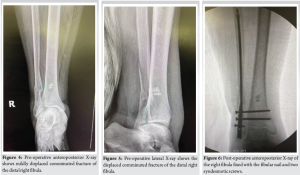

An 80-year-old female with a medical history of hypertension, chronic obstructive pulmonary disease, and two prior surgeries – a left ankle ORIF and a right total knee arthroplasty – presented to the Emergency Department with a right ankle injury following a mechanical fall. The patient reported an inability to bear weight on the right lower extremity since the fall. She denied any history of peripheral vascular disease, diabetes mellitus, or Vitamin D deficiency. On physical examination, there was ecchymosis and moderate soft-tissue swelling over the right ankle. Dorsalis pedis and posterior tibial pulses were palpable bilaterally. Neurological assessment revealed intact protective sensation bilaterally. Orthopedic examination showed no gross pedal deformities, but there was a limited range of motion in the right ankle due to pain. Tenderness was noted on palpation over the medial superior ankle, where moderate soft-tissue swelling and ecchymosis were observed (Fig. 1-3). An X-ray of the right ankle confirmed an oblique mildly displaced comminuted fracture of the distal right fibula (Fig. 4 and 5).

The patient underwent a comprehensive orthopedic surgical procedure to address a complex right ankle injury, specifically a trimalleolar equivalent ankle fracture with syndesmotic rupture. The procedure included ORIF of the fibula using the Fibulock Intramedullary (IM) Fixation system, butterfly fragment fixation utilizing FiberTape, and syndesmotic repair. The surgical approach involved anesthetic management with a laryngeal mask airway and a pre-operative popliteal block administered to the right lower extremity. The patient’s right lower extremity and foot were meticulously scrubbed, prepped, and draped using a standard aseptic technique. Fluoroscopy was employed throughout the procedure to confirm anatomical alignment, and the surgical site was thoroughly irrigated with normal saline. The procedure began with a 3 cm incision on the lateral aspect of the distal fibula, proximal to the fracture site. Using a combination of blunt and sharp dissection, the hematoma was irrigated with normal saline, and the fracture site was localized under fluoroscopy. Coagulated blood was removed, soft-tissue impingements were addressed, and a reduction clamp was applied to reapproximate the bone fragments. To further stabilize the fracture, an angled hemostat was used to place FiberTape around the fibula fracture, encircling the fibular shaft at the butterfly fragment. The cerclage suture tails were secured to provide tension to the FiberTape, and fragment apposition was confirmed under fluoroscopy. Next, attention was directed to the lateral aspect of the right ankle, where a longitudinal incision was made 1 cm distal to the fibula’s tip. Percutaneous reduction of the fibular fracture was achieved with appropriate alignment of the ankle joint and fracture reduction. A guidewire was advanced from the distal aspect of the fibula through the fracture site, followed by drilling the fibula with an IM drill. The diaphyseal canal was reamed, and a 3 × 130 mm fibular nail, assembled with a target guide, was inserted through the incision. The fibular nail facilitated the reduction of the ankle fracture, and two syndesmotic screws were applied within the fibular construct to enhance ankle stability and provide additional support to the posterior malleolus fragment (Fig. 6 and 7).